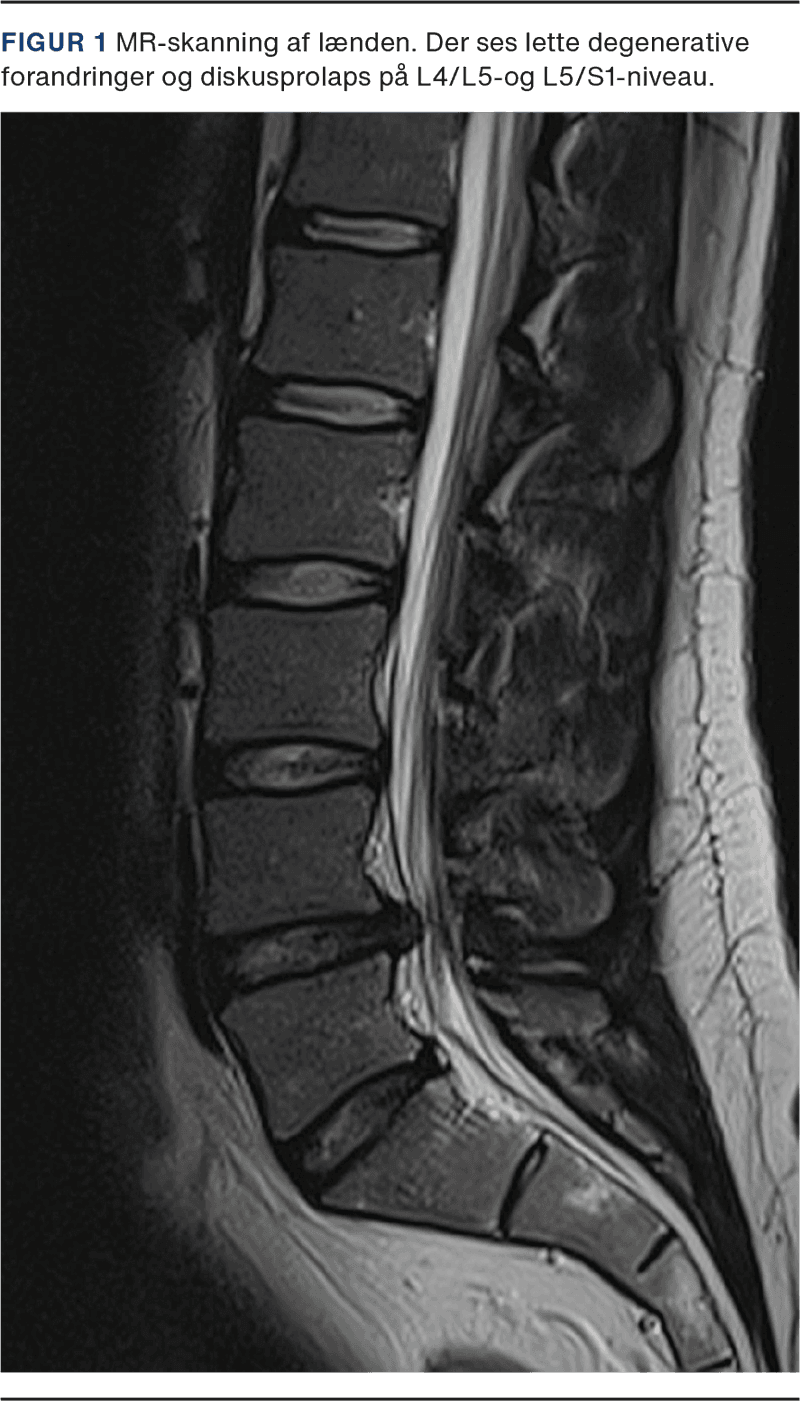

I forbindelse med udredning af lændesmerter er MR-skanning den mest anvendte billeddiagnostiske modalitet [1], da den bedre visualiserer relevante anatomiske detaljer som diskus og nerver end f.eks. røntgenundersøgelse og CT, som har bedre fremstilling af knoglerne (Figur 1). Brugen af MR-skanning har været støt stigende i det seneste årti, og i 2021 blev der foretaget ca. 85.000 MR-skanninger af lænden, hvilket er en stigning på over 20% siden 2013 [1]. Tendensen ses, på trods af at der i kliniske guidelines frarådes rutinemæssig brug af MR-skanning i diagnosticeringen af lændesmerter [2]. Størstedelen af patienter med nyopståede lændesmerter oplever en spontan bedring efter kort tid [3]. Der er ikke evidens for, at MR-skanning har positiv indflydelse på patientrapporterede effektmål såsom smerte eller funktion [4], og en MR-skanning vil derfor som regel ikke ændre hverken behandling eller prognose.